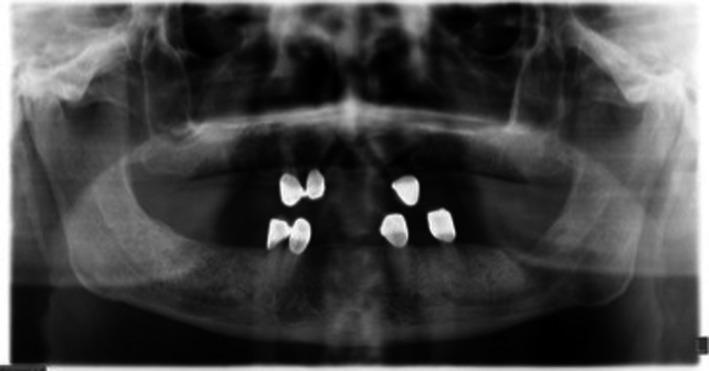

下颌弥漫性大B细胞淋巴瘤的胃肠道转移

Gastrointestinal tract metastasis of mandibular diffuse large B-cell lymphoma.

Not only diffuse large B-cell lymphoma is a malignancy, but also is initially and orally diagnosed in early stages. However, it could be misdiagnosed with other oral pathologies. However yet, early diagnosis is still crucial for the prognosis, morbidity, and mortality in such cases. Additionally, whole-body scanning with positron emission tomography/computed tomography should be performed for diagnosis and treatment process.

摘要

弥漫性大B细胞淋巴瘤不仅是一种恶性肿瘤,而且最初可在早期通过口腔诊断出来。然而,它可能会被误诊为其他口腔疾病。不过,早期诊断对于此类病例的预后、发病率和死亡率仍然至关重要。此外,在诊断和治疗过程中应进行正电子发射断层扫描/计算机断层扫描全身检查。